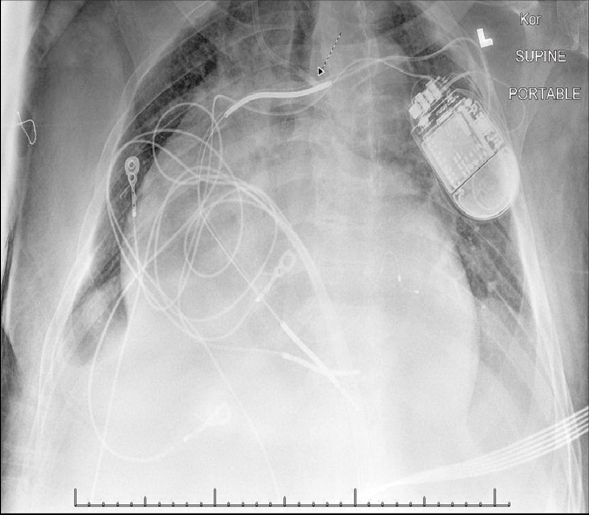

We report the case of a 74-year-old African American male patient, with a past medical history of end-stage renal disease, on haemodialysis for seven years via a left brachiocephalic Arteriovenous Fistula (AVF), admitted to the medical ICU for septic shock in November of 2017. The patient was haemodynamically unstable requiring vasopressors and; therefore, unable to undergo his regular haemodialysis treatment. On the second day of admission, the patient developed fluid overload needing Continuous Veno-Venous Haemofiltration (CVVH) for fluid removal. As a standard practice in our hospital, we do not routinely use AVFs for CVVH, and we placed a temporary dialysis catheter instead. After obtaining an informed consent from the family, we placed a triple lumen (12.5 French) temporary non-tunneled dialysis catheter via right anterior Internal Jugular Vein (IJV) approach using Seldinger technique (after the needle was introduced into the vessel, with ultrasound guidance, a guidewire was advanced through the lumen of the needle and the needle was withdrawn. The dialysis catheter was then passed over the guidewire into the vessel and the guidewire was withdrawn). In the post-procedural Chest X-ray (CXR), the catheter crossed the midline in the superior mediastinum, which was concerning for an arterial placement [Table/Fig-1]. An urgent blood gas from the catheter confirmed arterial placement [Table/Fig-2]. We started heparin drip and obtained an urgent CT angiogram of the head and neck. The CT angiogram showed that the catheter entered the subclavian artery near the origin of the right vertebral artery and within 1 cm of the right common carotid artery [Table/Fig-3,4 and 5], and the tip of the catheter ended at the brachiocephalic artery near the aortic arch [Table/Fig-6]. It also showed that the left vertebral artery was chronically occluded, and the right IJV was narrow distally. Vascular surgery, interventional radiology and cardiothoracic surgery consultant were involved due to the complexity of the case and we considered different treatment strategies. Due to the atriotomy size, deep location, proximity of nearby branch vessels and chronic occlusion of the left vertebral artery, endovascular interventions were too risky and infeasible. We further considered an open surgical repair. However, due to the atriotomy location, we needed to perform at least a partial sternotomy, and the patient was too critical to undergo such a surgery. The patient’s condition continued to deteriorate, and we had a prolonged multi-disciplinary conversation with the family considering all available options. After the family meeting and respecting the patient’s wishes, his code status was changed to comfort measures only and the plan was to avoid any further intervention. We left the catheter in place and discharged the patient to a nearby facility. The patient passed away after one day of discharge.

AP portal CXR showing the catheter course and tip (arrow) crossing the midline in the superior mediastinum which is concerning for arterial placement.